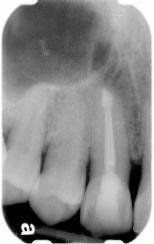

Apexogenesis

This procedure encourages the root to continue development as the pulp is healed. The exposed pulpal tissue is covered with MTA. This will allow for the exposed tissue to heal against the MTA, keeping the pulpal tissues vital and encouraging further maturation and growth of the tooth. This process will enable the tip of the root (apex) to continue to close as the child gets older. In turn, the walls of the root canal will thicken, and the tooth will become stronger. If the pulp heals, no additional treatment will be necessary. The more mature the root becomes, the better the chance for the survival of maturing.